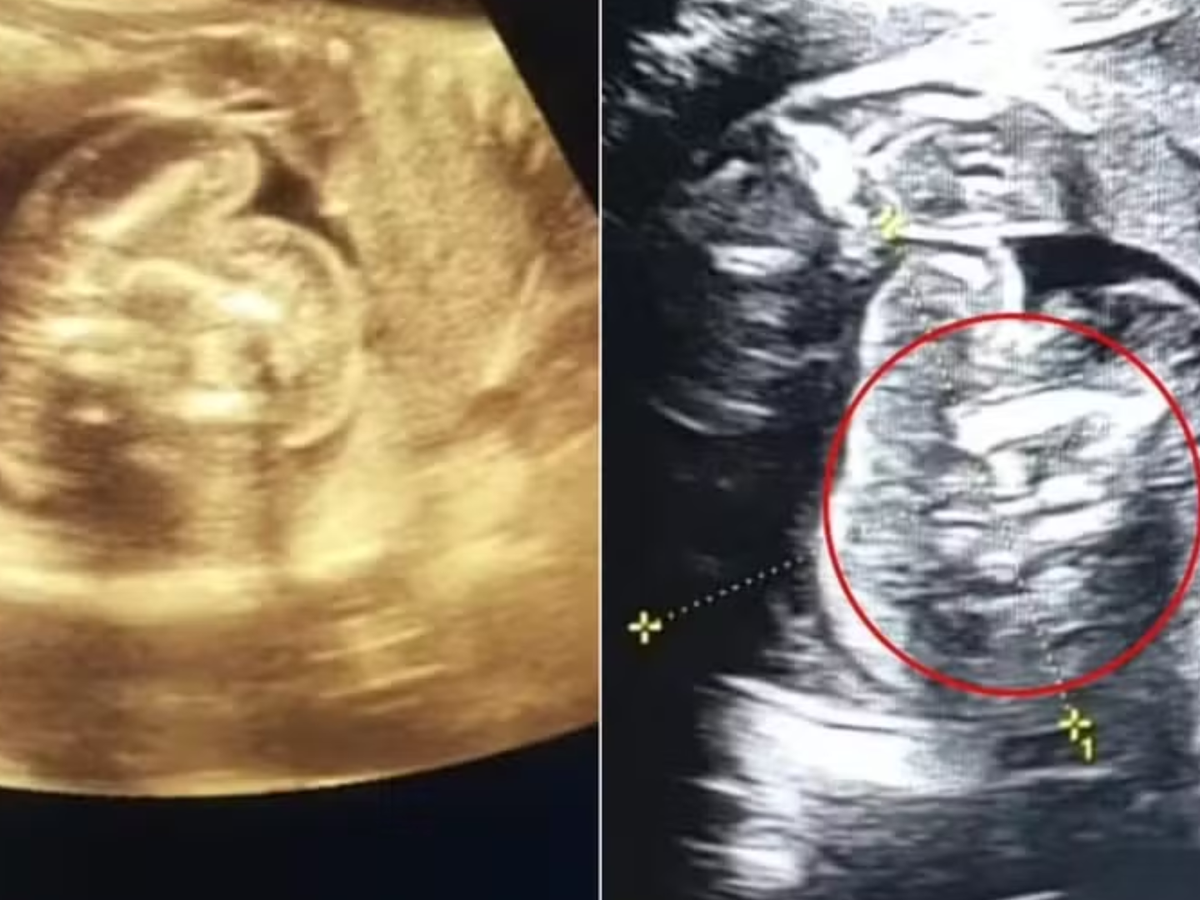

Foto: Reprodução / Contigo

Um caso extremamente raro surpreendeu médicos na Índia quando uma mulher de 32 anos, grávida de 35 semanas, deu entrada em um hospital para um exame de rotina. Durante a avaliação, os profissionais de saúde identificaram que o bebê, um menino, carregava dois fetos em seu abdômen, um fenômeno conhecido como "feto dentro de feto". O caso, registrado apenas cerca de 200 vezes na literatura médica, chamou a atenção da comunidade científica.

Os exames revelaram uma estrutura anormal contendo ossos dentro do bebê, o que levou os médicos a realizarem uma investigação mais aprofundada. "Tive sorte e fui vigilante o suficiente para notar algo muito incomum com este bebê, um feto em crescimento normal, com alguns ossos e uma estrutura semelhante à de um feto no abdômen. Imediatamente me ocorreu que isso não era normal", explicou o médico Prasad Agarwal, responsável pelo caso.

A mulher deu à luz no dia 1º de fevereiro e, logo após o nascimento, os médicos removeram os dois fetos que haviam parado de se desenvolver dentro do bebê. Felizmente, tanto a mãe quanto a criança passam bem e estão sob acompanhamento médico para garantir um desenvolvimento saudável. O fenômeno, que ainda intriga especialistas, geralmente ocorre durante a gestação de gêmeos idênticos, quando um embrião não se separa completamente do outro e acaba ficando preso dentro do corpo do irmão.

Os médicos explicam que, nesses casos, o feto absorvido pode continuar a desenvolver características como unhas, cabelos e até membros. "Os fetos são considerados parasitas porque dependem do hospedeiro para sobreviver e não possuem órgãos vitais completamente desenvolvidos. Isso significa que eles não são viáveis e precisam ser removidos", afirmaram especialistas. Neste caso específico, os fetos apresentavam pés e mãos, reforçando a complexidade do quadro.